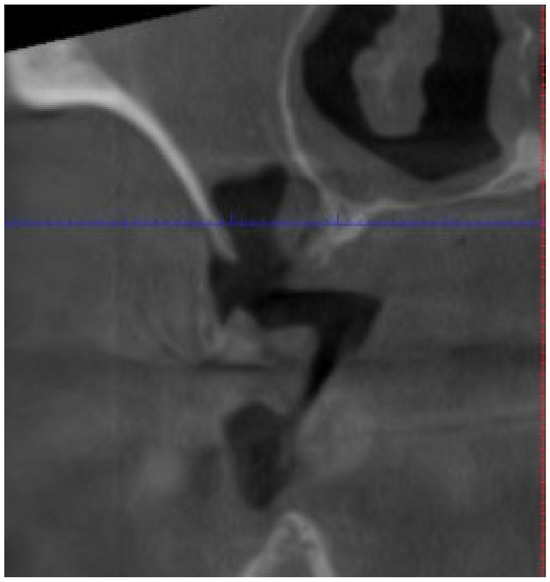

| Fistula (Intraoral/Extraoral) | An abnormal tract that connects the oral cavity (or skin) to necrotic bone, allowing probing of the underlying bone tissue (Figure 4). | Stage 1+ |